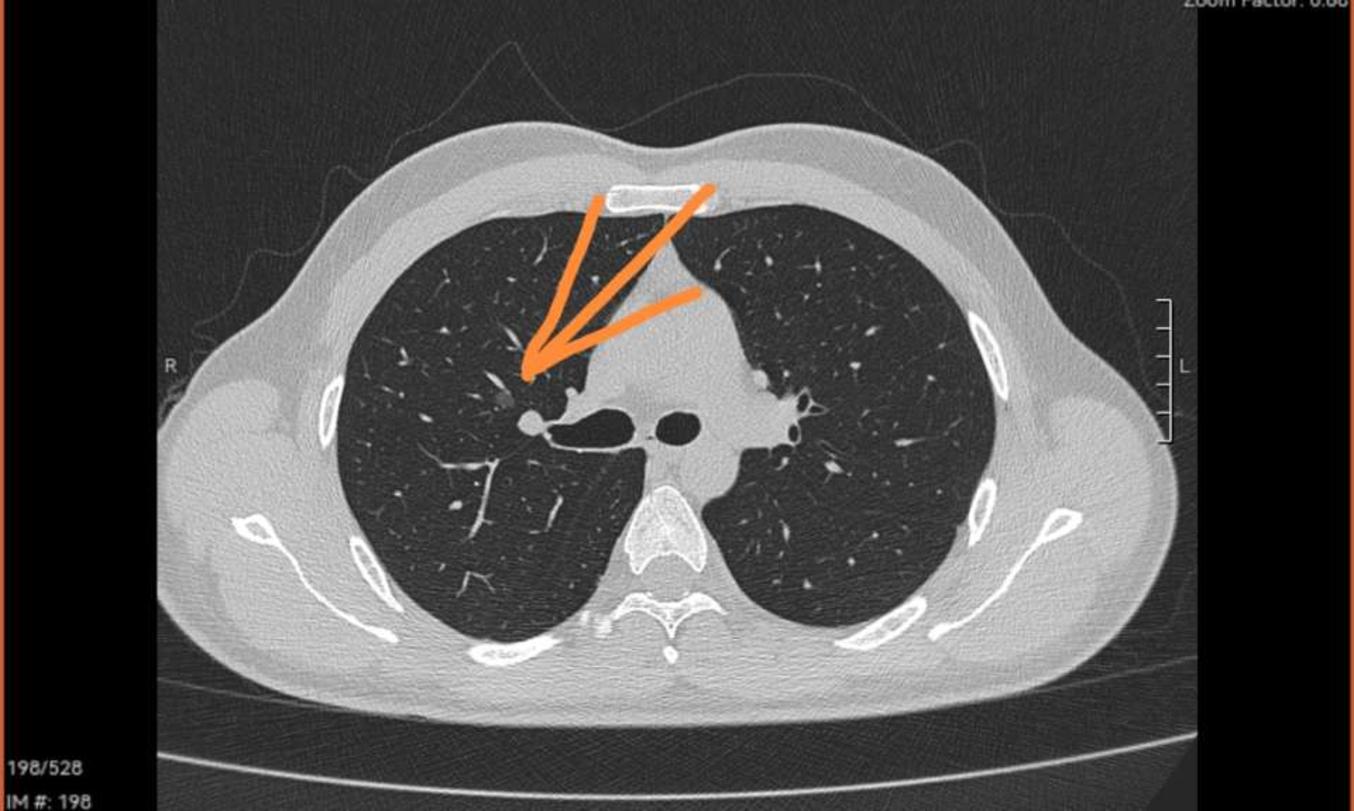

患者50岁女性,因其它原因做ct偶然发现多发肺结节.

刘懿博士说肺癌(四〇一八)肺结节靠近肺门,会是中央型肺癌么?